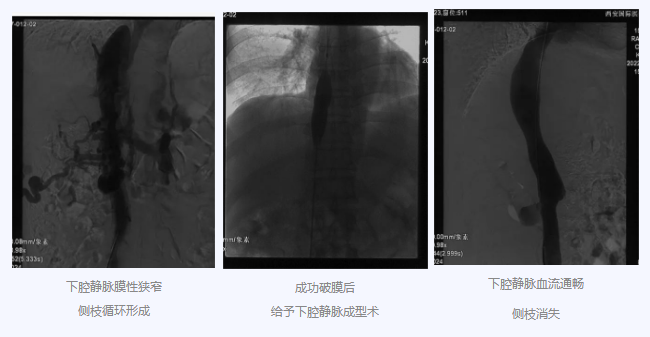

入院后,在韓國(guó)宏院長(zhǎng)的安排下,臨床經(jīng)驗(yàn)豐富的醫(yī)師給老謝做了B超、CT 等檢查,結(jié)果顯示:三支肝靜脈近心端閉塞,肝內(nèi)側(cè)枝循環(huán)形成,下腔靜脈近心房入口處隔膜樣狹窄,隨后的DSA血管造影也證實(shí):下腔靜脈狹窄,且有側(cè)枝形成,最終確診困擾老謝20年的疾病為混合型布加綜合征,是一種罕見病。

明確診斷后,韓院長(zhǎng)帶領(lǐng)團(tuán)隊(duì)縝密分析老謝的病情,為其制定最佳的治療方案,考慮到老謝的根本病因是下腔靜脈阻塞,介入手術(shù)成為首選治療方法,通過微創(chuàng)介入手術(shù),可準(zhǔn)確打通患者的閉塞血管,癥狀迅速緩解。做好充分術(shù)前準(zhǔn)備后,為患者行“下腔靜脈成型術(shù)”,精準(zhǔn)定位快速貫通,閉塞的下腔靜脈順利開通,手術(shù)圓滿完成。